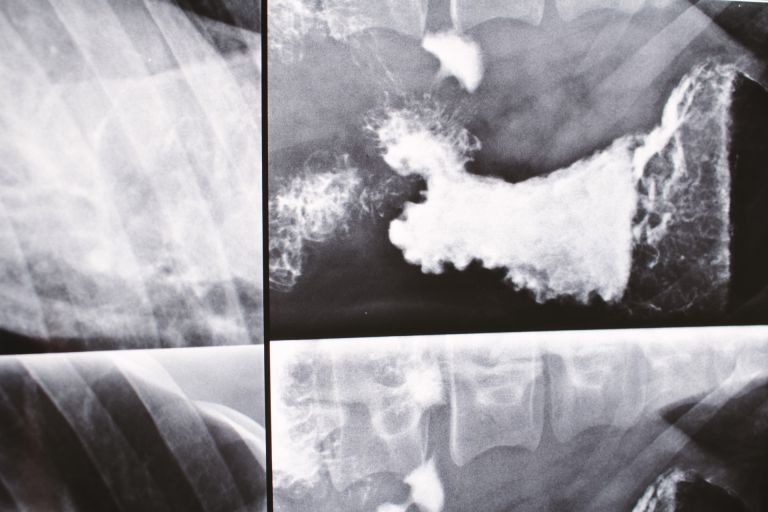

初めての検査・診断って何するの?

レントゲンから型取りまで徹底解説